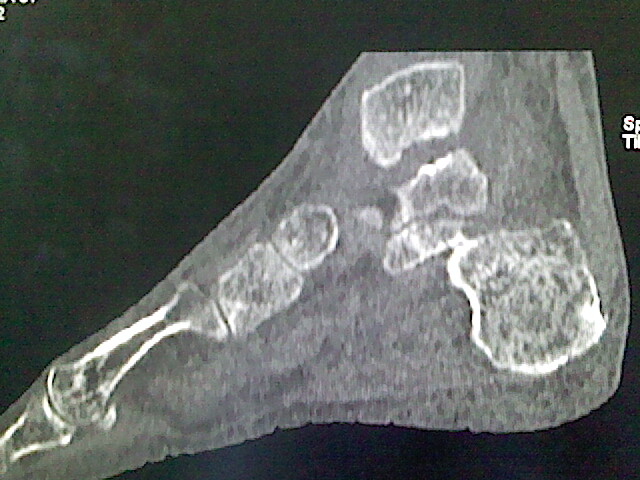

标题: CT16814:男,76岁,左小腿疼痛,不能站立 大家给看看 [打印本页]

男,76岁,左小腿疼痛,不能站立

本例骨质改变主要表现为滑膜或韧带区的骨侵蚀融解(胫腓联合区骨质破坏无硬化边),距骨后部骨质破坏区有硬化边及死骨样改变.所以,本例考虑关节结核可能性大,绒毛膜结节性滑膜炎多发于中年,且极少见于膝髋以外的关节,骨质硬坏也以压陷吸收为主,有明显的硬化边,骨膜增生呈结节状(可以mr鉴别),所以本例暂除外.

另不除外可引起相似表现的其他炎症如布氏杆菌性关节炎等